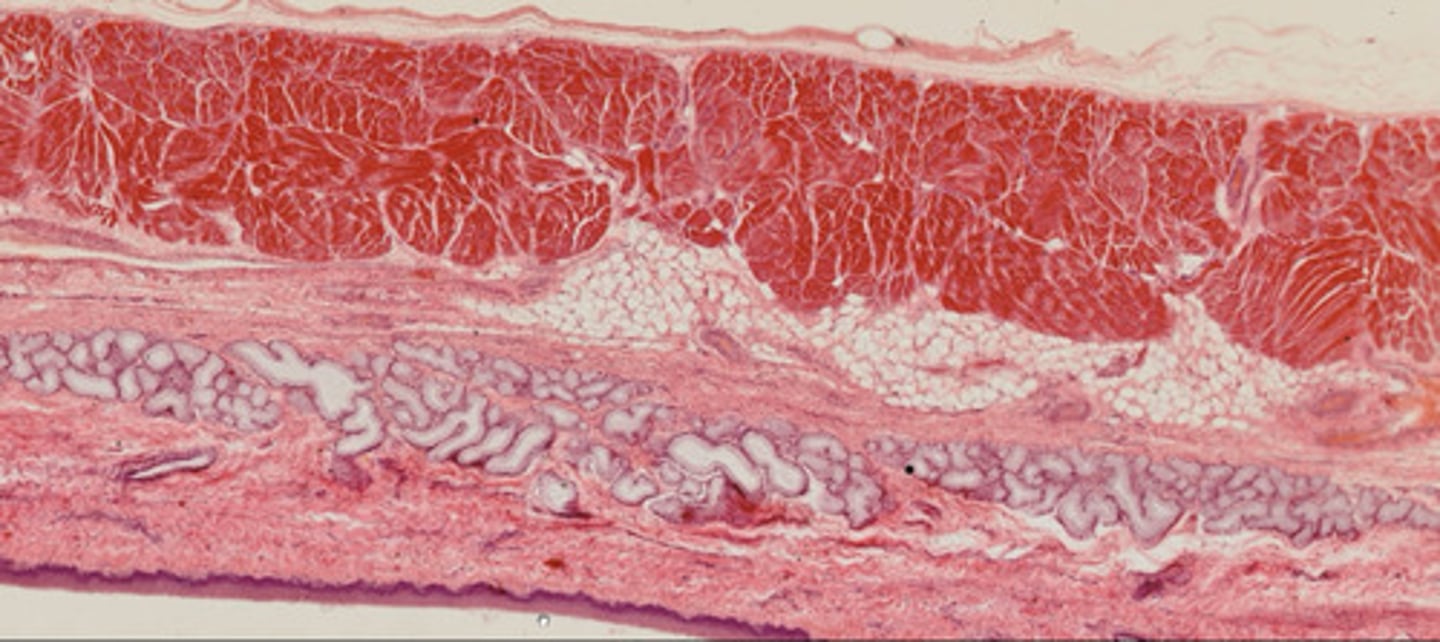

Przełyk (H+E)